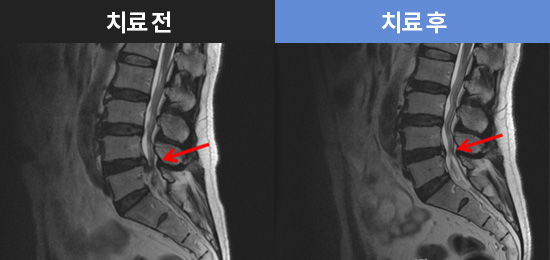

CHAMJALHAM MRI로 보는 치료결과

치료결과 더보기-